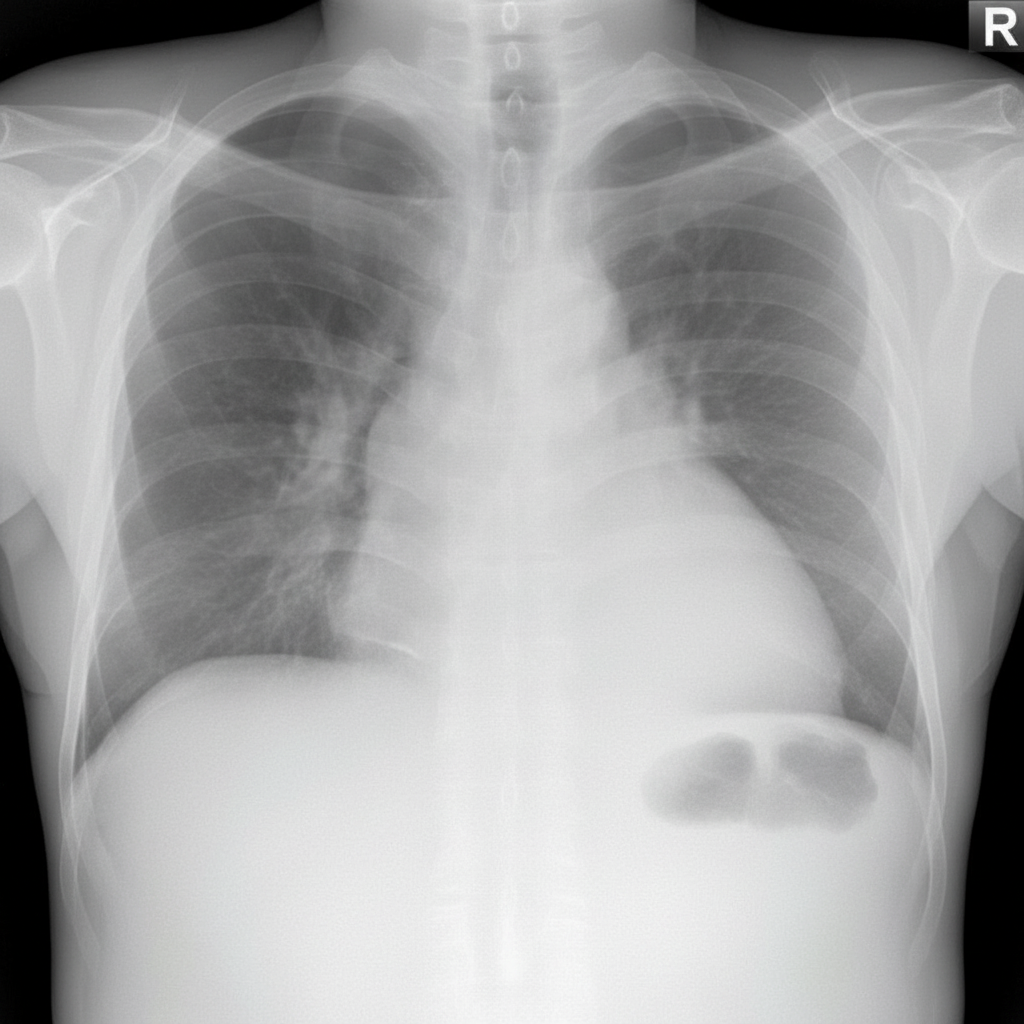

The tube visible in the chest X-ray below is located in which anatomical space?

Explanation: ***Pleural space*** - Chest tubes are specifically inserted into the **pleural space** to drain air (pneumothorax) or fluid (pleural effusion) between the visceral and parietal pleura. - On chest X-ray, the tube appears positioned laterally in the **intercostal space**, following the natural anatomical pathway into the pleural cavity. *Pericardial cavity* - The **pericardial cavity** surrounds the heart and would require **pericardiocentesis** or pericardial drain placement, not a standard chest tube. - Radiographically appears as the space immediately around the **cardiac silhouette**, much more medial than typical chest tube placement. *Mediastinum* - The **mediastinum** contains the heart, great vessels, trachea, and esophagus in the central chest compartment. - Chest tubes are not placed in this space; mediastinal drains would be positioned more **centrally** and typically after cardiac surgery. *Lung parenchyma* - The **lung parenchyma** refers to the actual lung tissue containing alveoli and bronchioles. - Tubes placed directly into lung tissue would cause **pneumothorax** and significant lung injury, which is not the therapeutic intent.